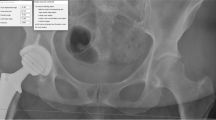

A calibrated CMM (coordinate measurement machine; Quantum FaroArm®, Lake Mary FL, USA; maximum error 0.05 mm) with a 1/8'' extended ball probe was used to acquire intraoperative accuracy data using radio-opaque markers positioned in each specimen by personnel specifically trained on the CMM (Fig. 1). At different steps during the surgical flow, the procedure was halted to perform the CMM acquisitions (Table 1). The CMM measurements using radio-opaque markers were used to validate the accuracy of the RA-THA platform, and are not part of the clinical use of the system.

Location of radio-opaque markers for CMM acquisitions (example of a left hip: 6 markers). Markers (insert) were manufactured and inspected to make sure they were within specifications. Making sure not to interfere with the THA incision, they were inserted press-fit into a pre-drilled hole in the bone at the following locations: a illiopectineal eminence, aligned over each teardrop (named ipsilateral and contralateral teardrop); b pelvis reference; c lesser trochanter; and d proximal and distal femoral axis. Markers were used to validate the accuracy of the RA-THA platform, and are not part of the clinical use of the system